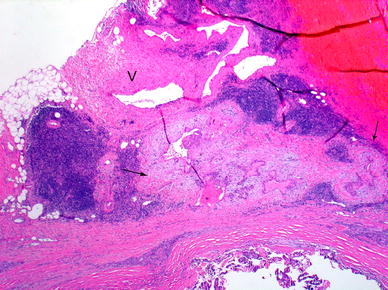

Extrathyroidal extension refers to involvement of the perithyroidal soft tissues by a primary thyroid cancer. On gross examination, the capsule may appear complete but evidence has shown that microscopically the capsule is focally incomplete in a majority of autopsy thyroid glands evaluated [20]. The capsule includes sizable vascular spaces as well as small peripheral nerves and is continuous with the pretracheal fascia. [21]. In practice, since the fibrous capsule of the thyroid is often incomplete, the criteria for defining (minimal) extrathyroidal extension may be problematic and subjective. Diagnostic findings for minimal extrathyroidal extension includes the presence of carcinoma extending into perithyroidal soft tissues, including infiltration of adipose tissue and skeletal muscle, as well as around (and into) sizable vascular structures and nerves. Extension into adipose tissue can be problematic given the fact that adipose tissue can be found within the thyroid gland proper under normal conditions and also may be a component of a variety of thyroid lesions including carcinomas. [22]. As such, the presence of adipose tissue in association with a thyroid carcinoma should not be mistaken for extrathyroidal extension. Some authorities only accept invasion of skeletal muscle as the identifier for extrathyroidal extension. However, similar to adipose tissue in the thyroid, the presence of skeletal muscle may be seen in the thyroid gland under normal conditions, especially in relation to the isthmus portion of the thyroid gland, as well as in a variety of pathologic conditions [22]. If present, a desmoplastic response may be a helpful finding in the determination of extrathyroidal extension (Fig. 5). The identification of thick-walled vascular spaces and/or small peripheral nerves in association with adipose tissue may be of greater assistance as these structures are not located in the thyroid gland proper and their presence would be helpful in determining whether the carcinoma is extrathyroidal in extent (Fig. 5).

Minimal extra-thyroid extension (ETE) into peri-thyroid fat. The focus of ETE (between arrows) has a desmoplastic reaction (pale staining fibrous tissue). Note nearby thick walled blood vessel (V). Both findings are indicative of ETE

While minimal extra-thyroid extension can be difficult to identify, extensive extra-thyroid extension is always obvious and easily diagnosed by the surgeon during the thyroidectomy. Extensive extrathyroid extension is defined by the presence of carcinoma well beyond the thyroid gland proper with direct invasion (i.e., not metastasis) into one or more of the following structures:subcutaneous soft tissues; adjacent viscera, including the larynx, trachea and/or esophagus; the recurrent laryngeal nerve, carotid artery or mediastinal blood vessels. Many studies have shown that carcinomas with extensive extra-thyroid extension have a much worse survival than those with minimal extra-thyroid extension [3, 23]. Moreover, some studies have found a similar outcome in patients with minimal versus no extra-thyroid extension [23].